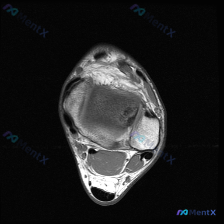

这是一张踝关节MRI-T1序列的轴位图像,临床提示要找「软骨异常」。我们先看对这张图像的基础读片结果:

- 骨骼:胫骨远端、腓骨远端、距骨形态完整,骨髓信号均匀,没有异常信号改变

- 关节:胫距关节间隙正常,没有异常积液填充

- 肌腱韧带:所有可见肌腱走形连续,信号正常;胫腓前后韧带结构完整,信号无异常

- 软组织:皮下脂肪和肌群信号正常,没有肿块或水肿

基础读片结论:这张单层T1轴位图像上,没有发现明确的病理性异常信号。